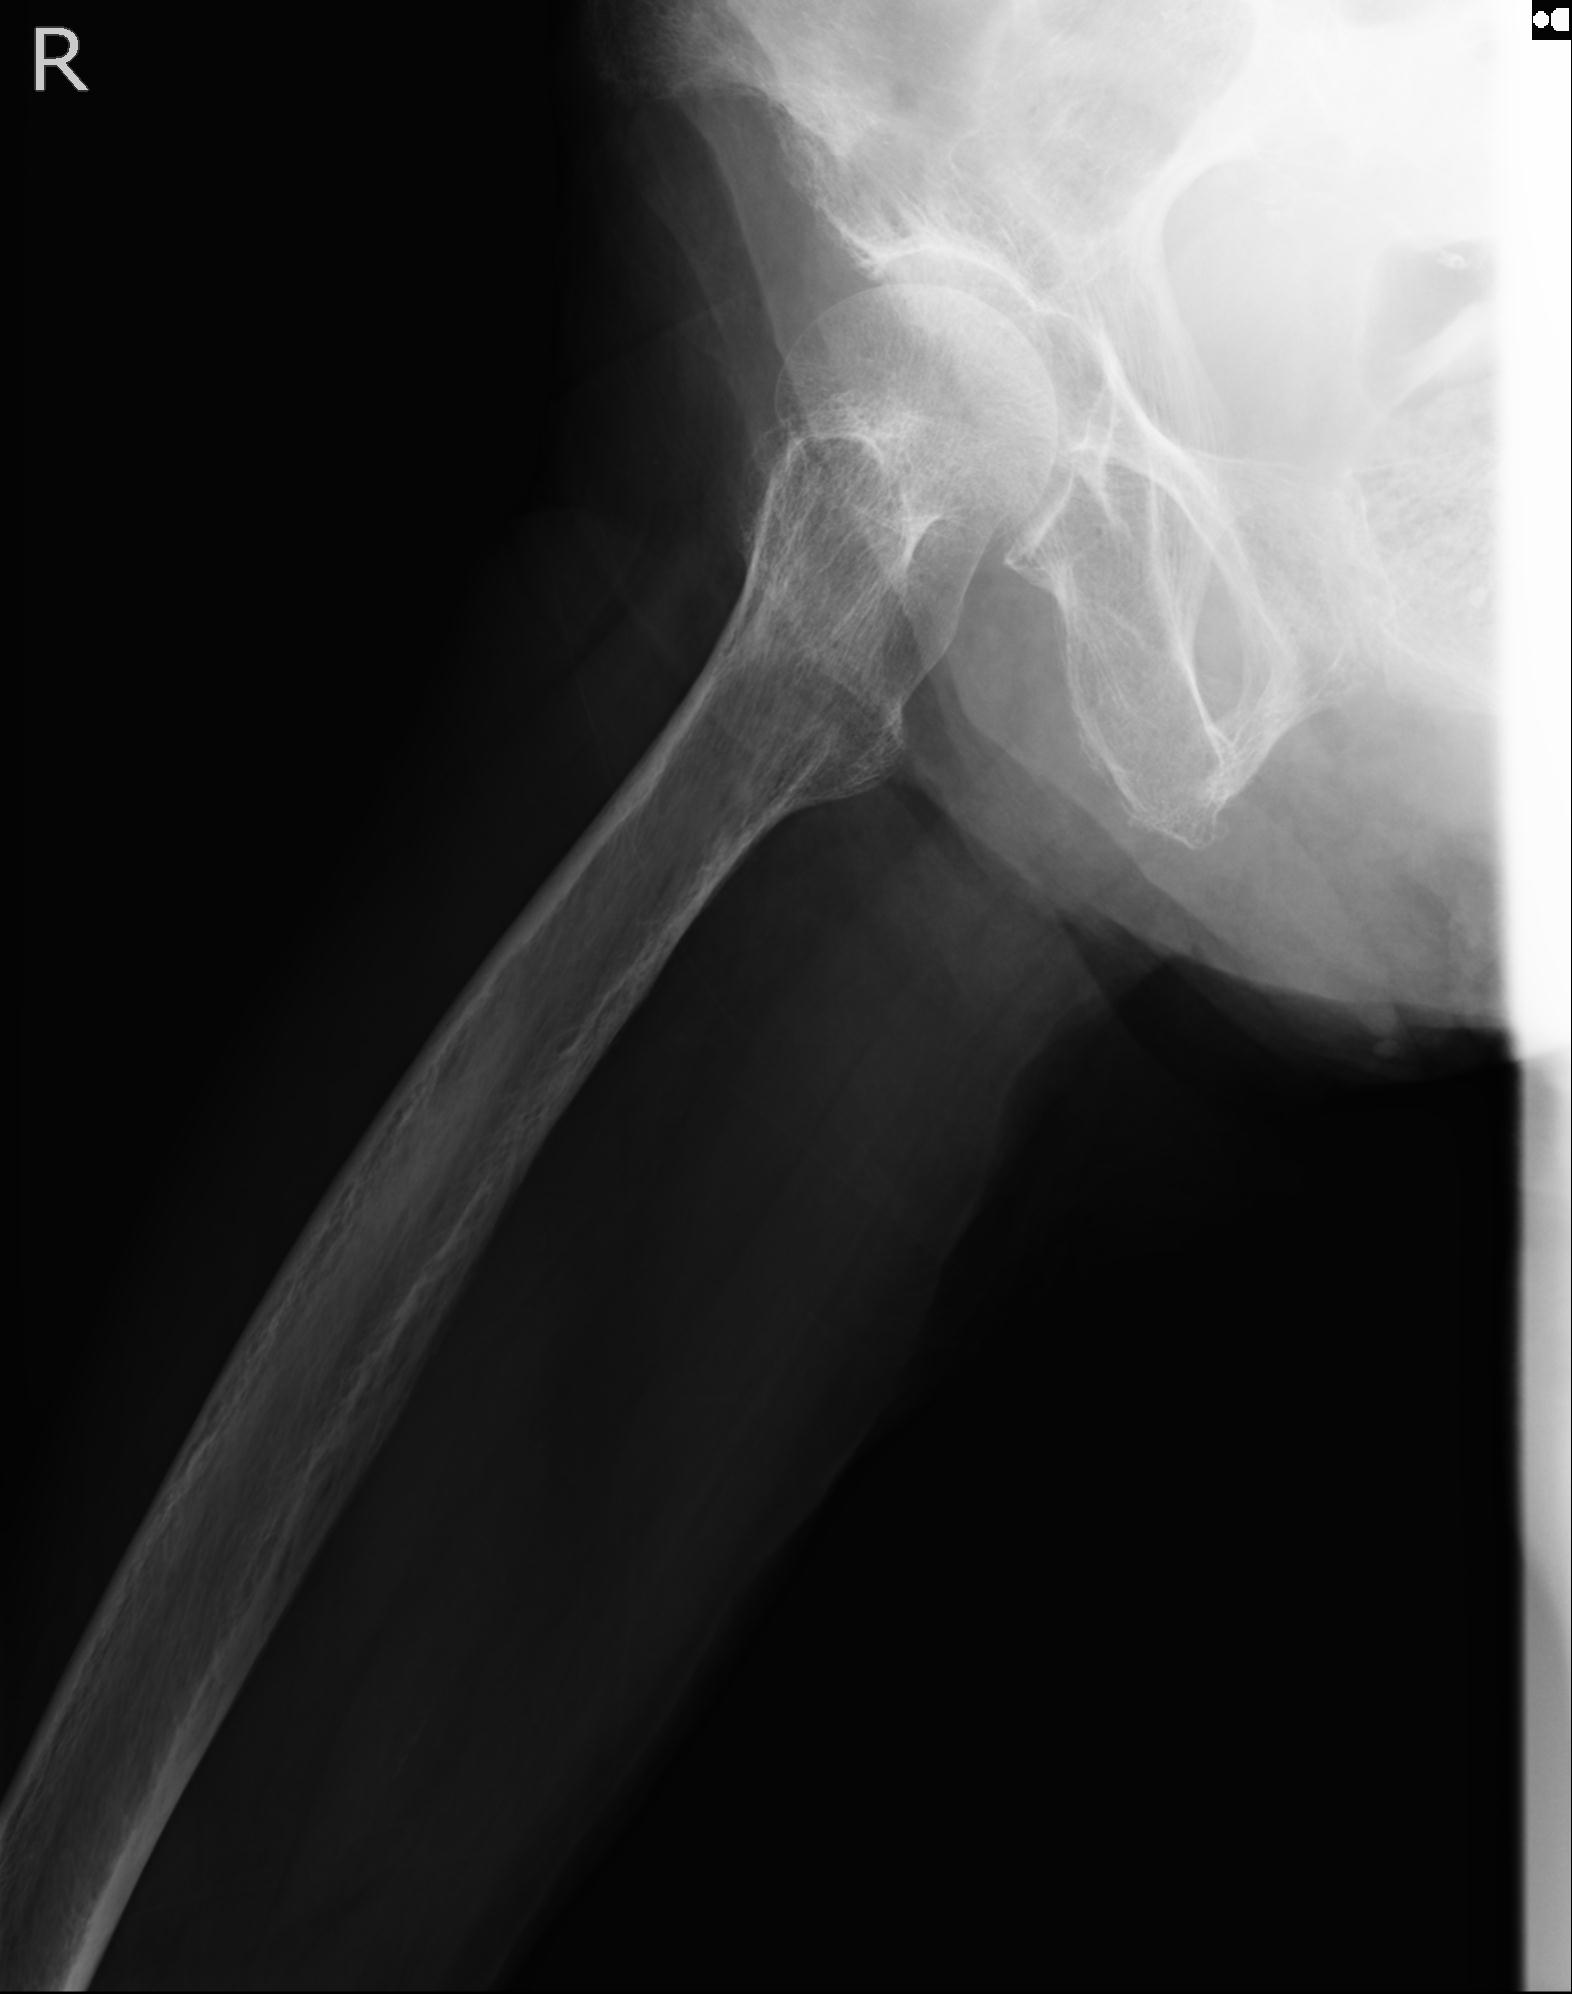

37 1/18 両股正面+軸 1/22 2R 86歳女性 右転子下